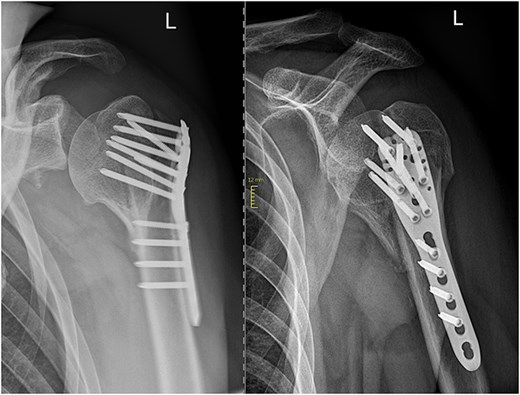

In subsequent clinical and radiological follow-ups at 2, 6, and 24 weeks postoperative, the humeral head depression showed regression, and the patient was able to progressively increase joint demands (Fig. 3). Training under physiotherapeutic supervision was difficult because of his secondary diagnoses. In the end after 6 Months he was unaffected in his daily living and painless.